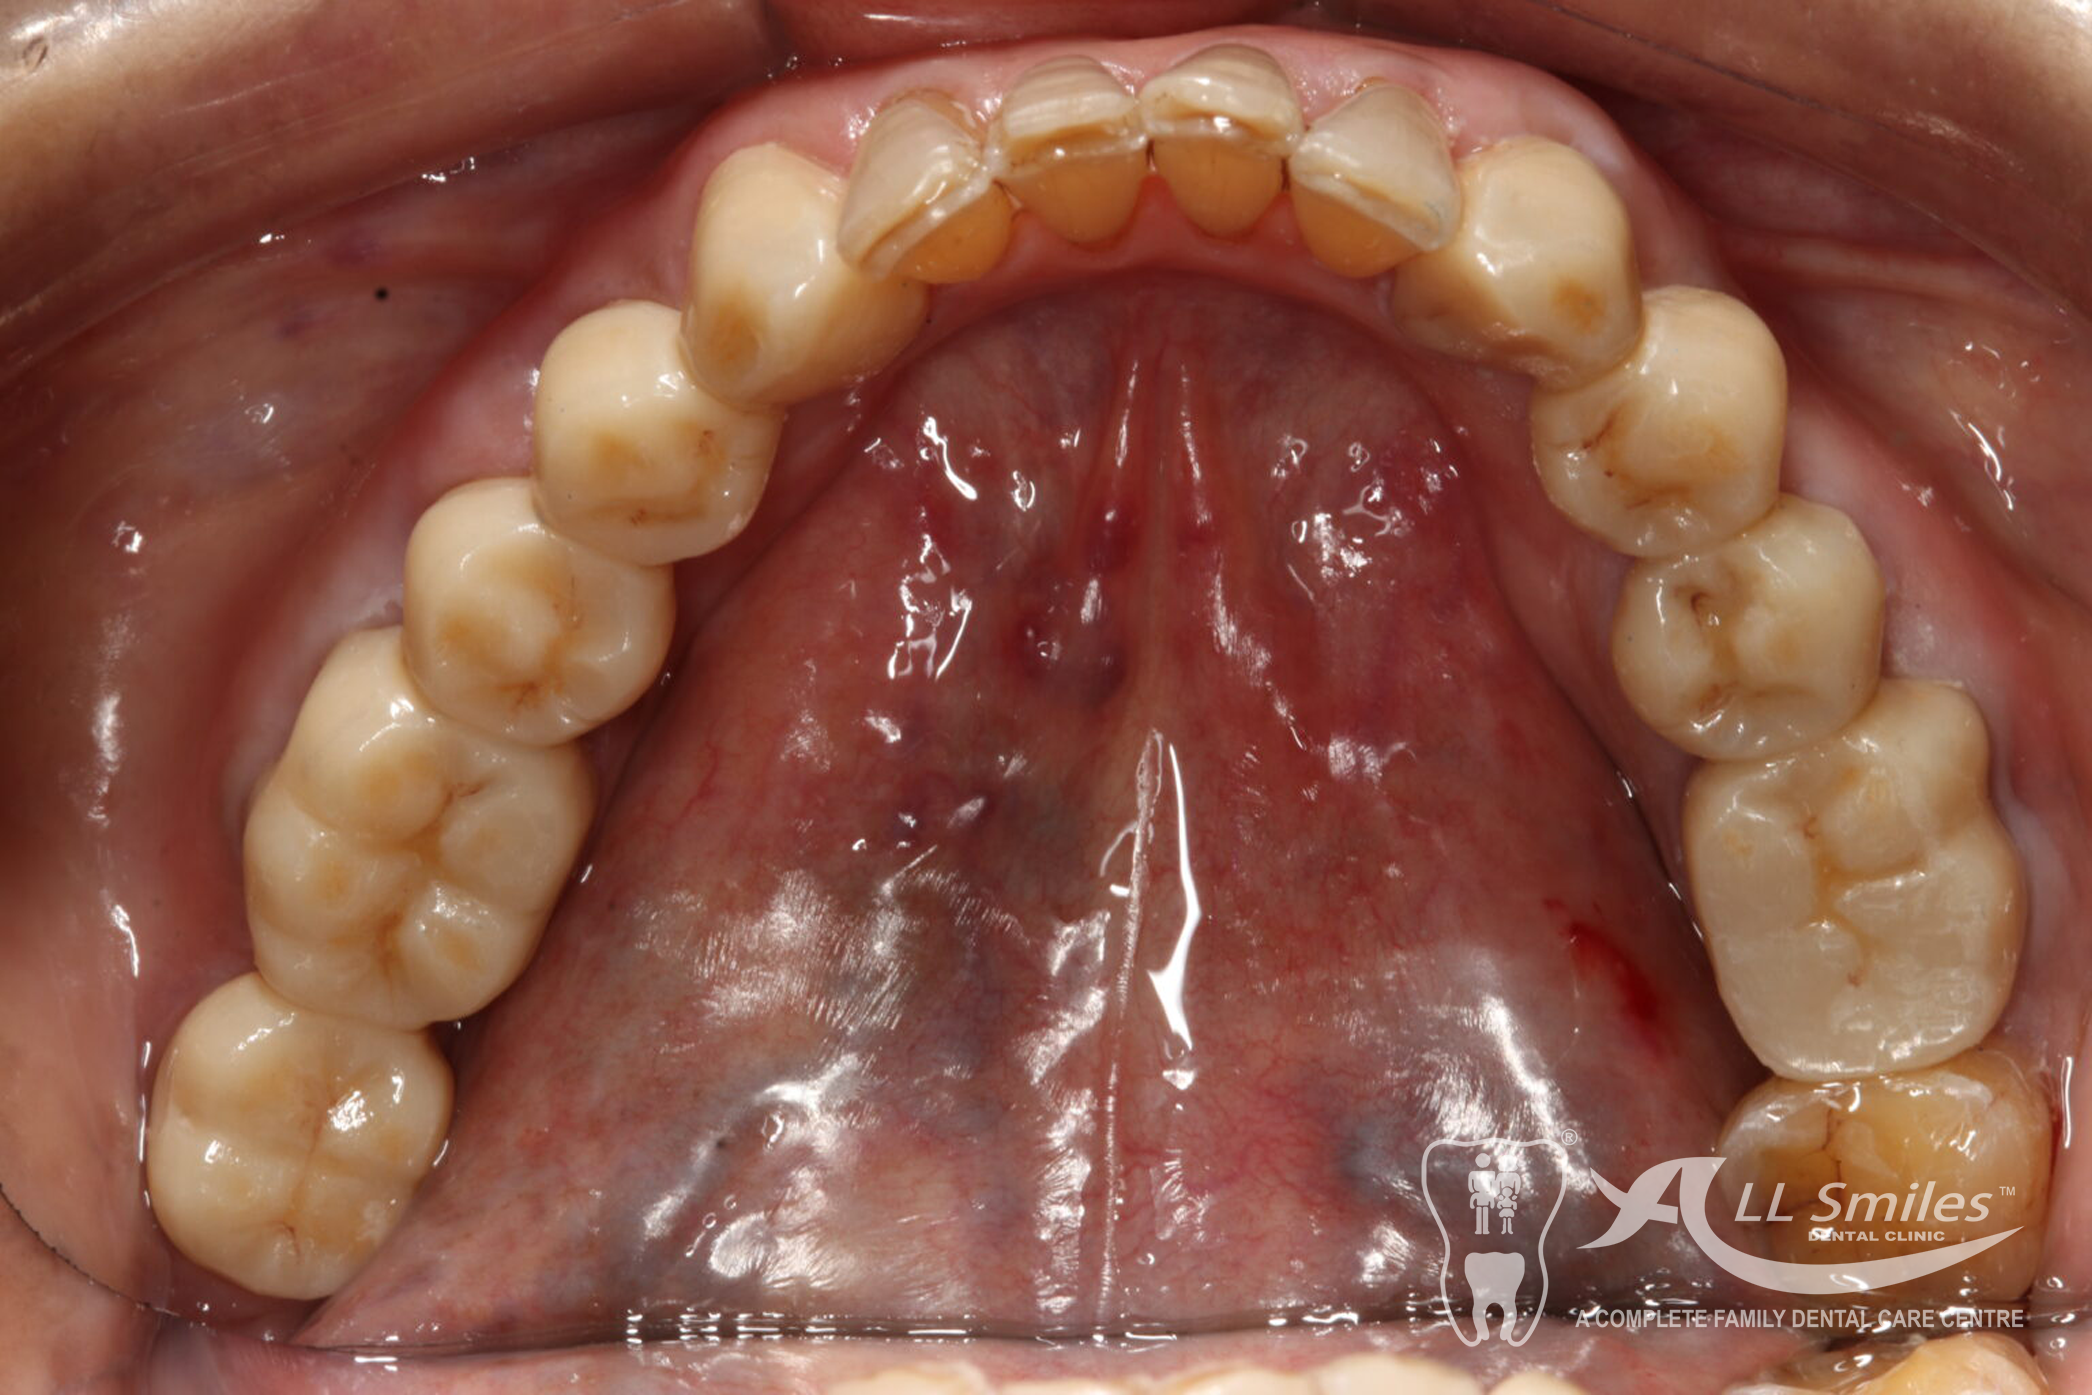

Crowns & Bridges Gallery